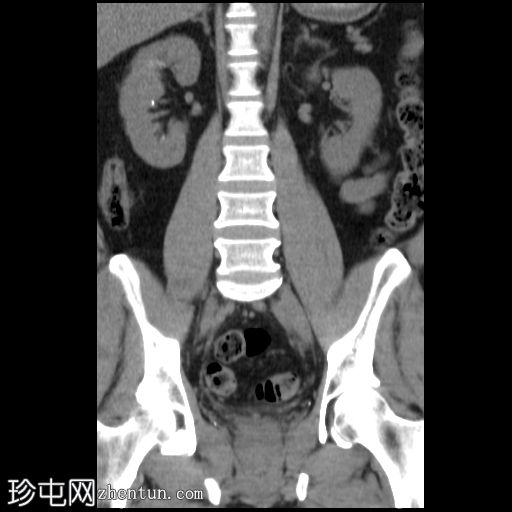

CT

定位像

右肾上盏内可见一中等大小的结石,大小约为16 x 13 x 15 mm。右肾中盏内可见一小结石,大小约为4 x 2 mm。右肾下盏内可见另一小结石(过小无法测量)。未见肾盂肾盏扩张。

非增强 CT KUB 显示右肾多发结石,其中上肾盏结石较大,大小为 16 x 13 x 15 mm,密度较高(平均约 1060 HU),符合钙结石的特征。中肾盏和下肾盏可见其他较小的结石。

肾盂肾盏系统未见扩张,提示无梗阻性病变。该发现与患者反复腰痛的病史相符,腰痛可能与结石移位有关,而非当前存在梗阻。